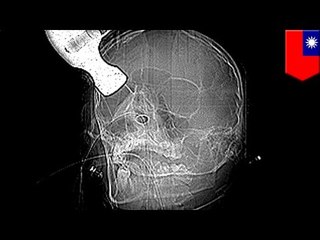

Fuqing, Chiny, 4 listopada.br To zwierzę to dzik.br A to policjanci próbujący go złapać.br Patrzcie na tego w środku – marny z niego strzelec.br Ta biedna kobieta stała niedaleko całej akcji i została postrzelona w plecy.br Na pewno ci przechodnie jej pomogą. Ta jasne, chyba nigdy nie byłeś w Chinach.br Ofiara, 26-letnia kobieta zostałą postrzelona w płuco ale jakimś cudem dotarła do szpitala.br Dzik nie został złapany.